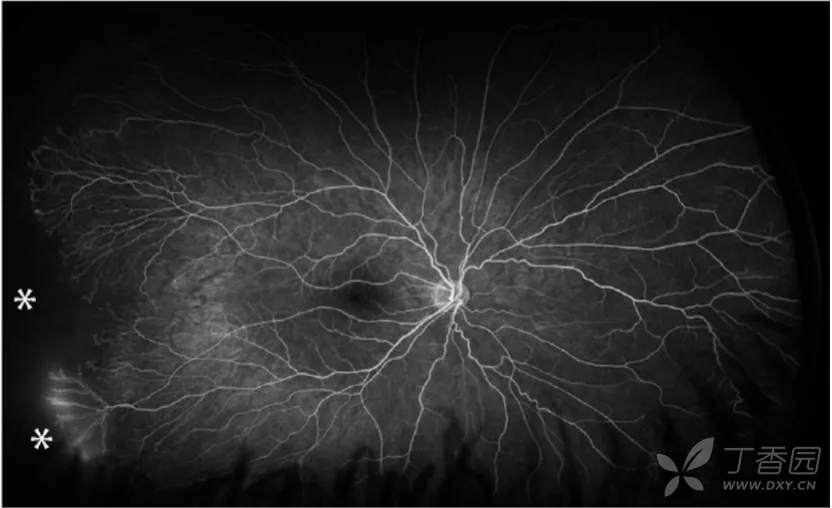

图. 7岁患儿有自发消退ROP病史,超广角FA可见持续性视网膜无血管区(星号),颞下方异常的血管结构(圆圈)。

图. 7岁患儿有自发消退ROP病史,超广角FA可见颞下方不完全消退的3期病变处存在持续性视网膜无血管区和渗漏(星号)。